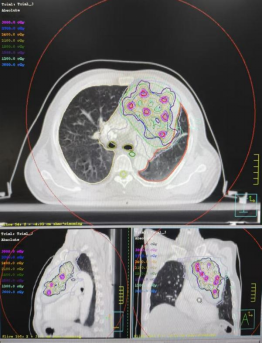

确定方案后,团队立即启动全流程精准治疗。先为患者完成精确定位与靶区勾画,再制定个性化精细放疗计划。治疗期间,放疗技师团队结合图像引导技术,确保每次治疗的精准性与重复性。

患者巨大肿瘤晶格放疗靶区及剂量分布